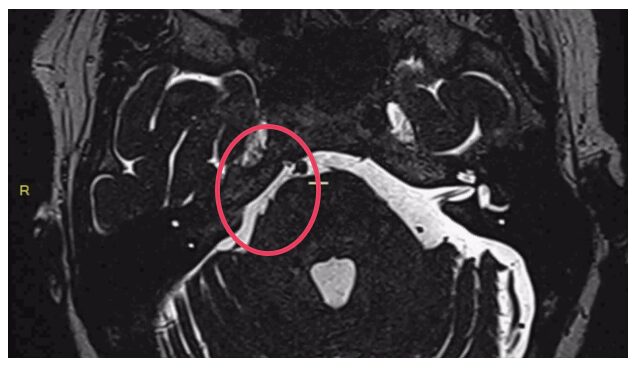

Les névralgies faciales ou trigéminales essentielles sont dues à un conflit entre le nerf trigéminal (5e nerf crânien) et une artère (artère cérébelleuse supérieure ou artère cérébelleuse antéro-inferieure).

Lorsqu’un conflit vasculo-nerveux est visualisée sur l’imagerie, une décompression peut être réalisée. Il s’agit d’empêcher le contact entre l’artère et le nerf par apposition d’un substitut entre les 2.

Conflit vasculo-nerveux

Figure 1. Conflit vasculo-nerveux pré opératoire